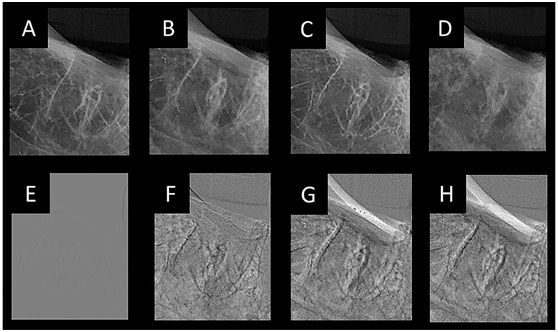

Figure 5 Socket in the lower molar region showing decrease in mineral density along time: A: baseline; B: 2 hours; C: 4 hours; D: 24 hours. E, F, G and H correspond to the images of S0, S1, S2 and S3 of the same region.